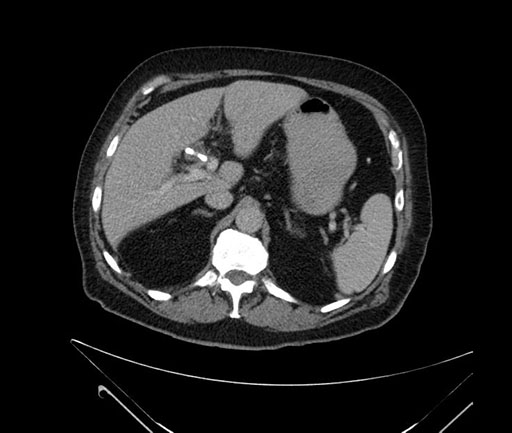

Imaging Analysis

Look through the patient's CT scan to identify any areas of concern for the necessary procedure.

Based on your CT findings, which issue(s) would give reason for "planned slowing down moment(s)" in this case?

Considering a standard Whipple procedure, what step(s) of the operation would you do differently in this case?